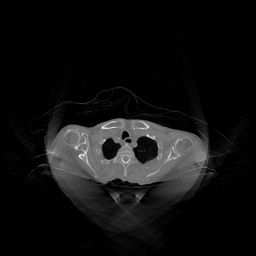

To assess the uncertainty of our method, we performed multiple reconstructions using different random seeds. As shown in Fig. 3, the ground truth and representative sampled images are presented in Fig. 3(a) and (b–d), respectively. The mean reconstruction and pixel-wise standard deviation across runs are displayed in Fig. 3(e) and (f). Only minimal differences are observed between reconstructions, indicating that I2SB produces highly consistent results. These findings confirm that, compared with classical diffusion models, I2SB substantially reduces uncertainty across repeated reconstructions.